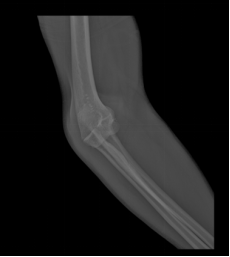

“五·一”假期的第一天,丘伯在家中换灯泡时,不慎摔倒,导致左肘部疼痛难忍,随即在家人的陪同下,立刻来到卫生院就诊。在完成相关检查后,唐云峰主任考虑左肘关节脱位、左尺骨冠状突撕脱性骨折,并立即采取手法复位。

治疗前